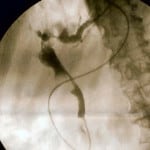

Introduction Obstructive Jaundice is a fairly common presentation to the emergency department and surgical teams. The most common cause is gallstones. You may also want to read about Gallstones and…